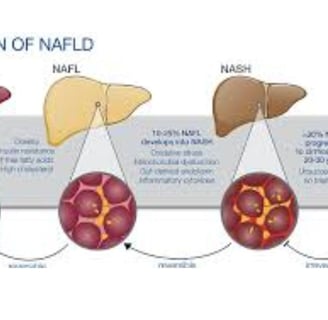

مرض الكبد الدهني، المعروف أيضًا باسم مرض الكبد الدهني غير الكحولي (NAFLD)، يتضمن تراكم الدهون الزائدة في الكبد.

هناك نوعان رئيسيان من الكبد الدهني: مرض الكبد الدهني غير الكحولي (NAFLD) الذي يتضمن تراكم الدهون في الكبد، ومرض التهاب الكبد الدهني غير الكحولي (NASH) الذي يترافق مع علامات الالتهاب وتلف خلايا الكبد.

التهاب الكبد: يبدأ من حالة دهون إلى حالة ملتهبة (متورمة).

التليف: يتكون نسيج ندبي نتيجة الالتهاب الذي يؤدي إلى تلف الكبد.

تليف الكبد: حيث يتم استبدال الأنسجة السليمة بنسيج ندبي.

سرطان الكبد: يمكن أن يتطور نتيجة لهذه الحالات.

الكبد الدهني من الدرجة الأولى: يعتبر حالة خفيفة حيث تشكل الدهون 5-10% من الكبد. من المهم تناول طعام صحي وممارسة الرياضة بانتظام.

الكبد الدهني من الدرجة الثانية: يحدث عندما تتراوح نسبة الدهون في الكبد بين 10-25%.

الكبد الدهني من الدرجة الثالثة: هو الأكثر خطورة، حيث يشير إلى نسبة مرتفعة من الدهون في الكبد مع التهاب في الأنسجة المحيطة.

يمكن أن يحدث هذا في كل من الكبد الدهني غير الكحولي والكبد الدهني الكحولي، وتزيد مخاطر الإصابة بالكبد الدهني من الدرجة الثالثة مع السمنة ومرض السكري من النوع 2 ومتلازمة التمثيل الغذائي.